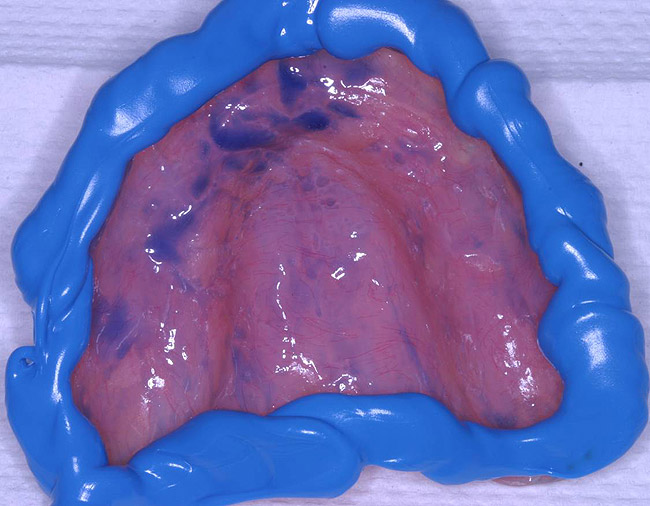

Figure 7  After border molding

Figure 7